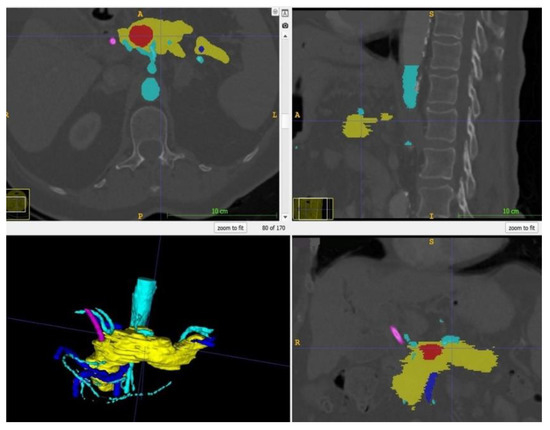

Within ITK Snap, the relevant structures, i.e., in this case the stomach, the pancreas, the tumor and the arteries and veins, were marked on each slide with different colors. Then, a 3D mesh was made from the 2D layer data (Step 2.b). The different meshes were exported as STL files. Figure 2 displays a screenshot of ITK Snap and Figure 3 demonstrates views from different angles on the created meshes.

Figure 2.

Screenshot of ITK Snap with the tumor in red, the pancreas in yellow, the arteries in light blue, the veins in dark blue and the splint in pink.

Figure 3.

After completion of the final mesh, the pancreas and its surroundings can be viewed from different angles. Note the rather rough surface as the CT scans had a slice thickness of 1 mm. (The pancreas in yellow, the arteries in light blue, the veins in dark blue, and the splint in pink.)